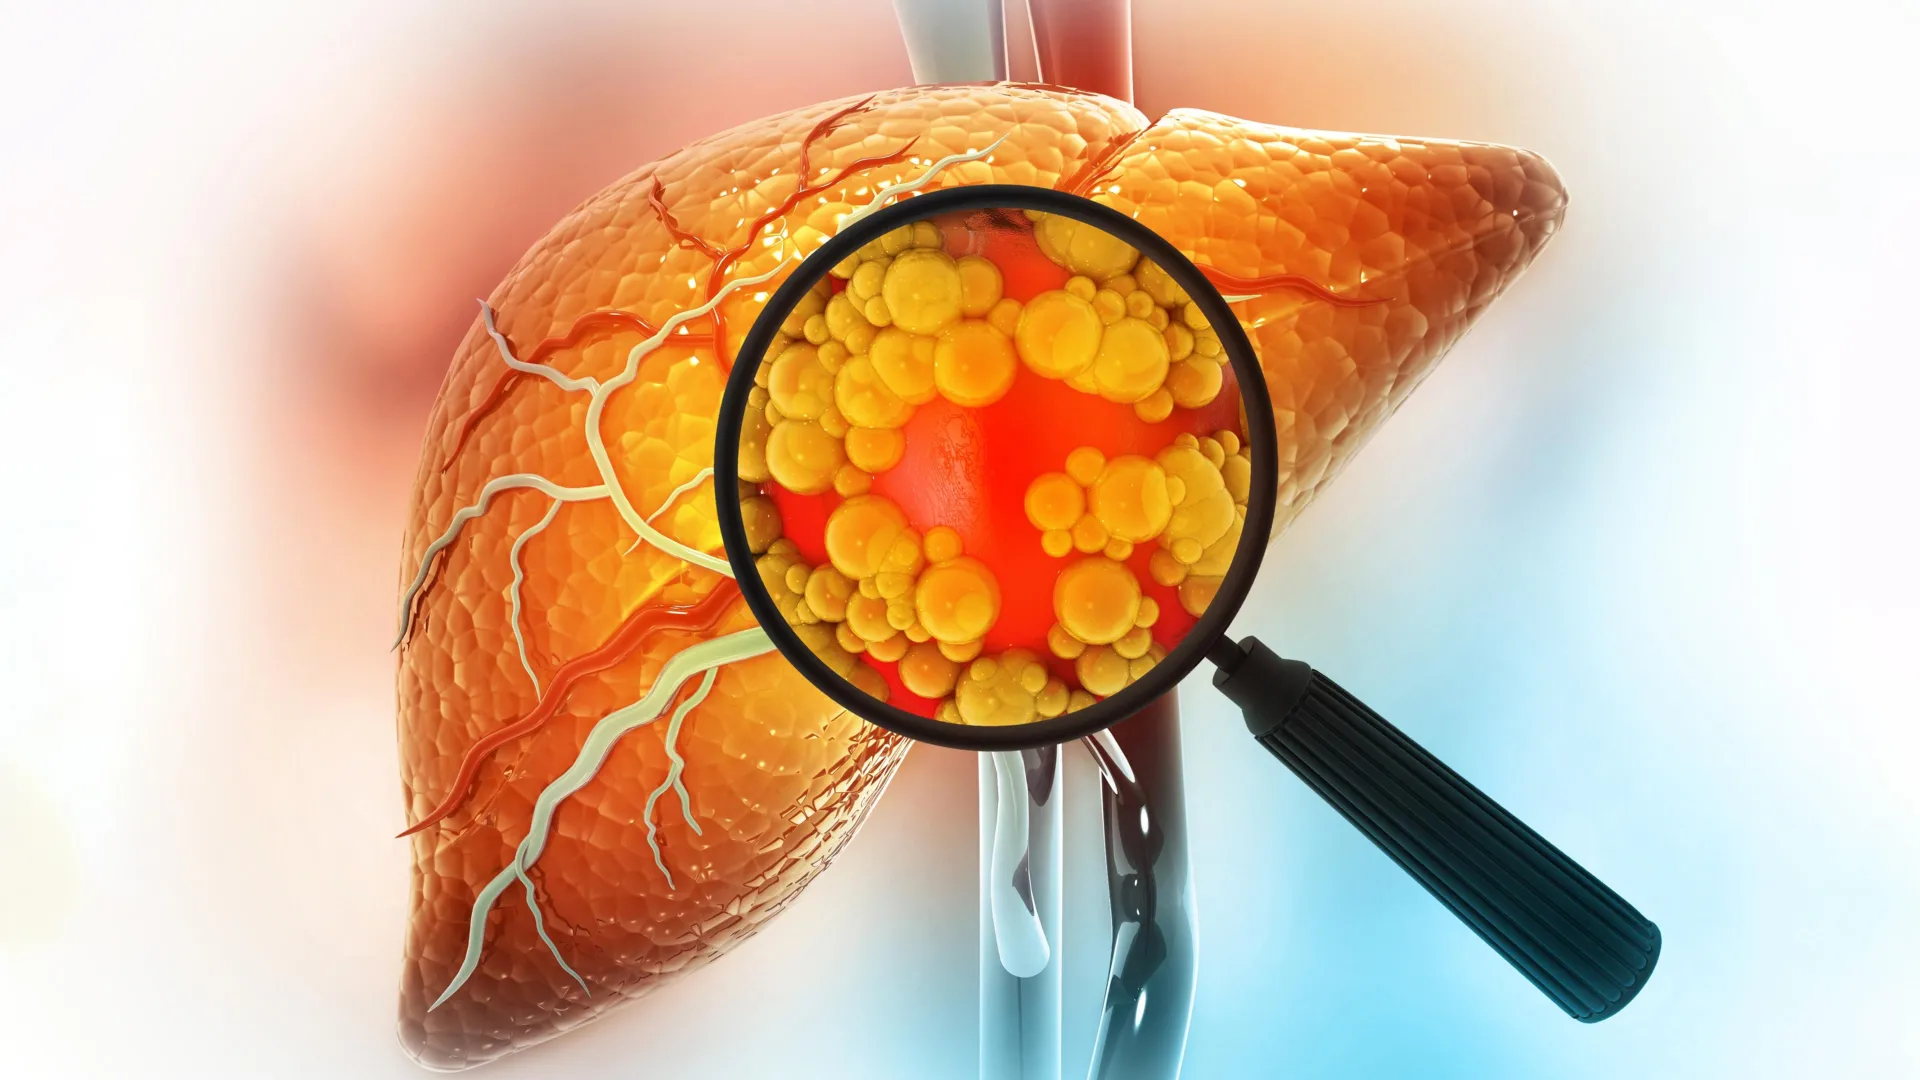

A diet high in fat is one of the strongest contributors to liver cancer risk. New research from MIT sheds light on why this happens, showing that fatty diets can fundamentally alter liver cells in ways that make cancer more likely to develop.

A diet high in fat is one of the strongest contributors to liver cancer risk. New research from MIT sheds light on why this happens, showing that fatty diets can fundamentally alter liver cells in ways that make cancer more likely to develop.